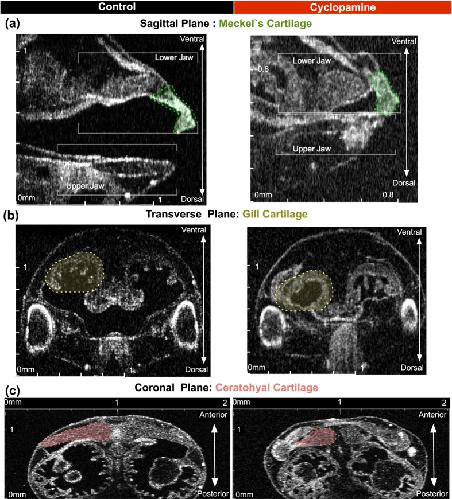

Analysis of Craniocardiac Malformations in Xenopus using Optical Coherence Tomography., Deniz E, Jonas S, Hooper M, N Griffin J, Choma MA, Khokha MK., Sci Rep. February 14, 2017; 7 42506. |